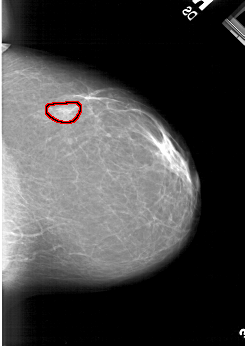

A_1177_1.LEFT_CC

RIGHT_MLO LINES 6376 PIXELS_PER_LINE 4111 BITS_PER_PIXEL 12 RESOLUTION 43.5 OVERLAY

FILE: A_1177_1.RIGHT_MLO.OVERLAY

TOTAL_ABNORMALITIES 1

ABNORMALITY 1

LESION_TYPE MASS SHAPE LOBULATED MARGINS OBSCURED

ASSESSMENT 3

SUBTLETY 4

PATHOLOGY BENIGN

TOTAL_OUTLINES 1

BOUNDARY